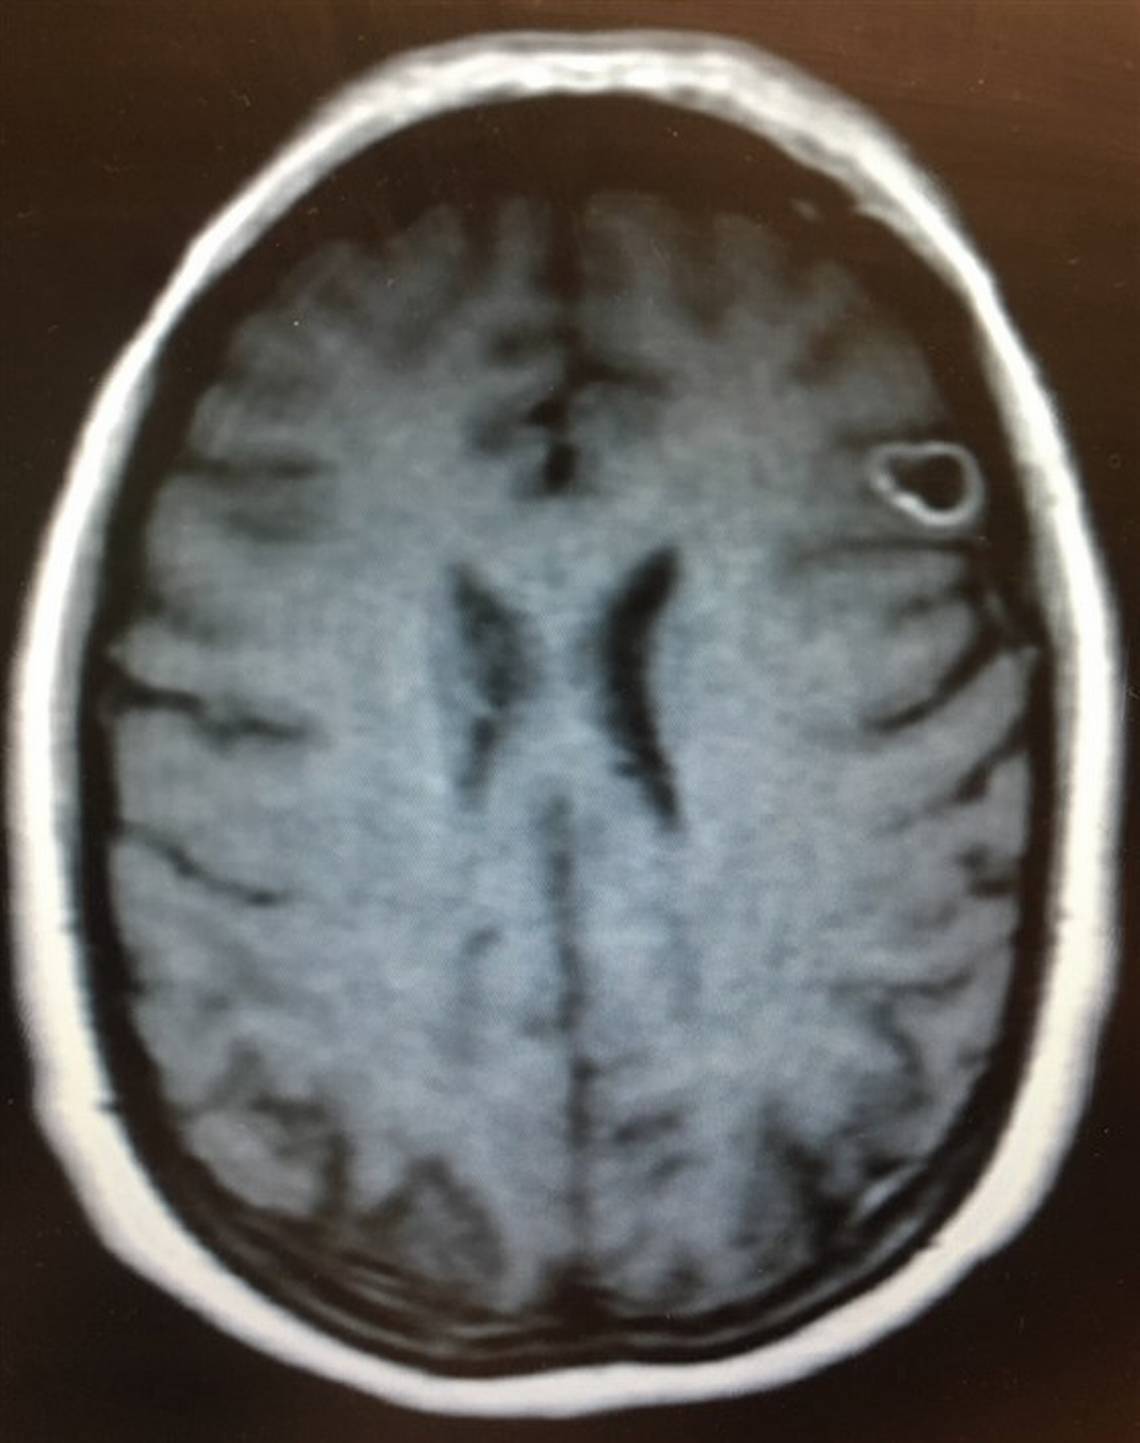

Tras pasar por varios doctores que no sabían lo que le ocurría llegó a un especialista en la clínica Mount Sinai que luego de someterla a una resonancia magnética descubrió que había un bulto en el lóbulo izquierdo, el que fue catalogado inmediatamente como un tumor cerebral.

Producto del diagnóstico Palma fue inmediatamente sometida a una cirugía, pero lo que encontraron los médico no eran lo que esperaban, ya que no se trataba de un tumor, sino que de un pequeño y delgado gusano.